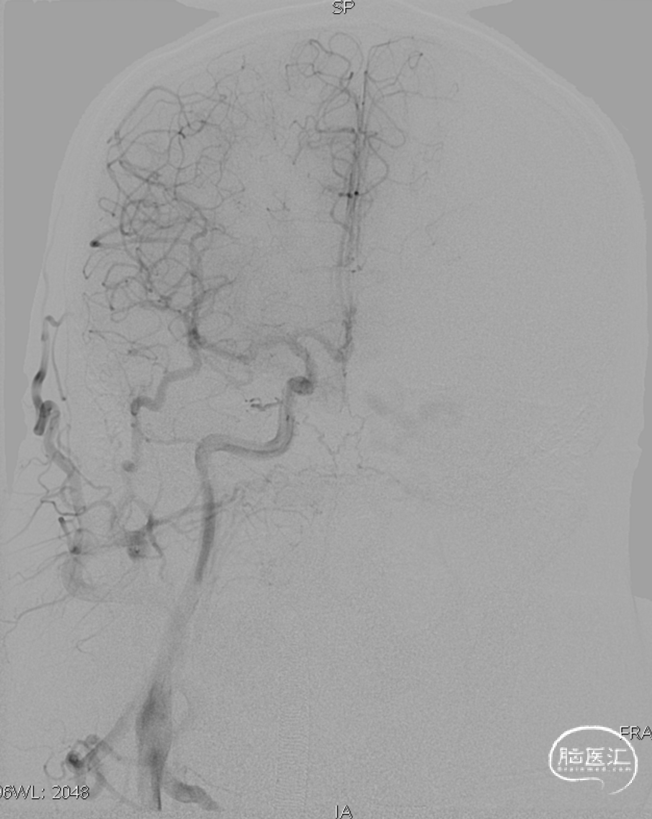

术后造影见瘘口不显影。

术前

术后

术后右侧颈总造影,未见向瘘口供血。